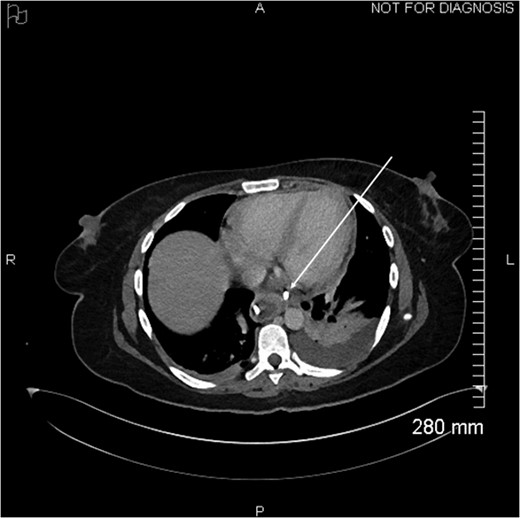

Proximal end of the double pigtail drain externalizes in the pericardium (arrow).

Axial view of opacification on CT showing the externalization of the drain in the pericardium (arrow).